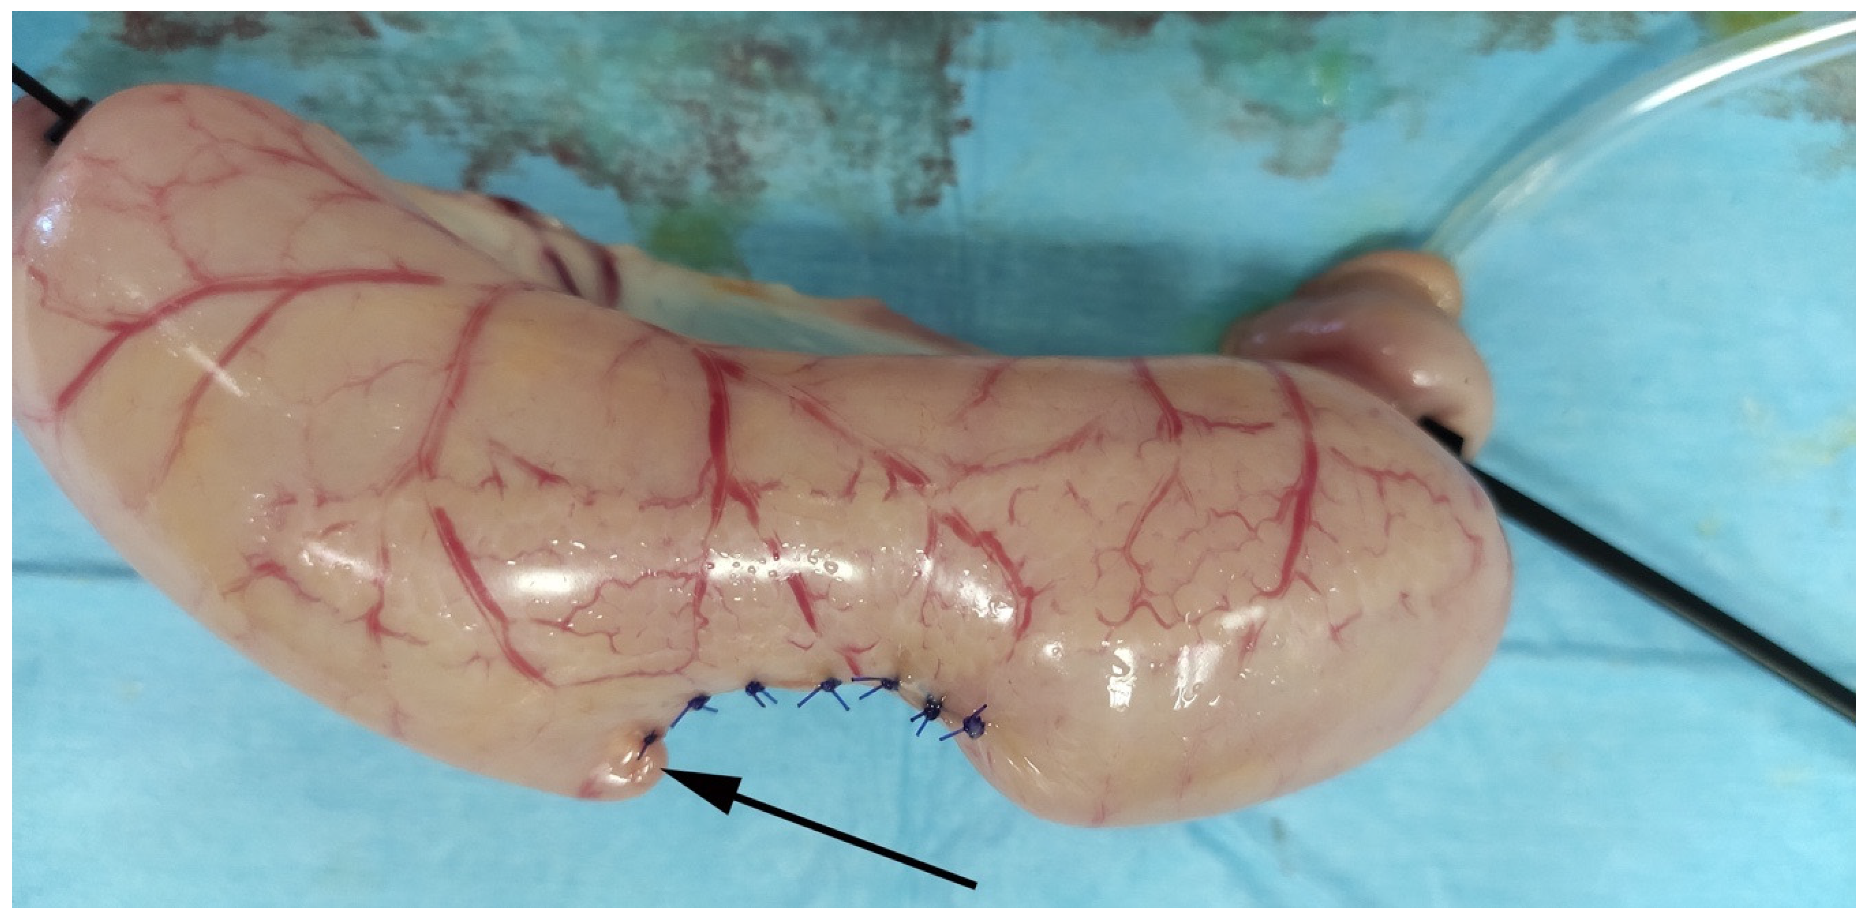

2.4. Sample Constructs